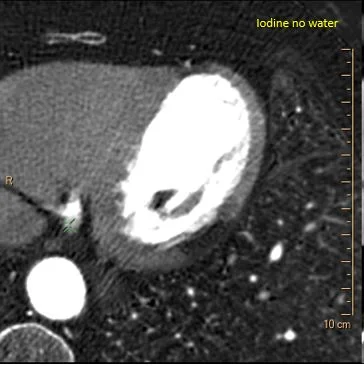

Iodine map: Stands out.

Iodine map shows no uptake on measurement.